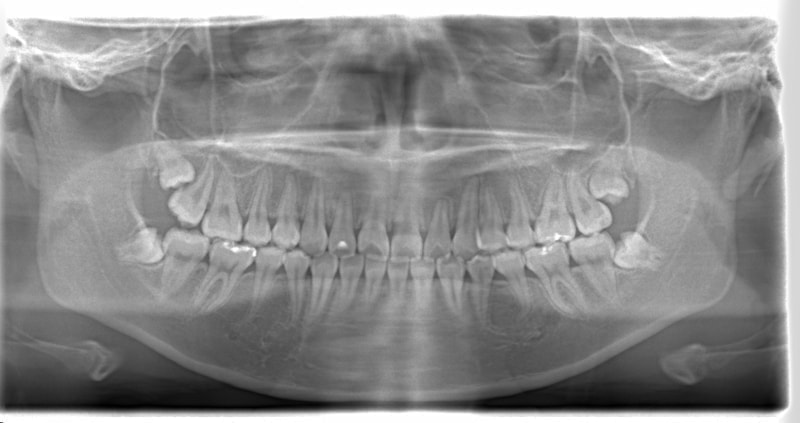

左上3番左下5番埋伏歯

治療法:フルパッシブブラケット:T21

治療前